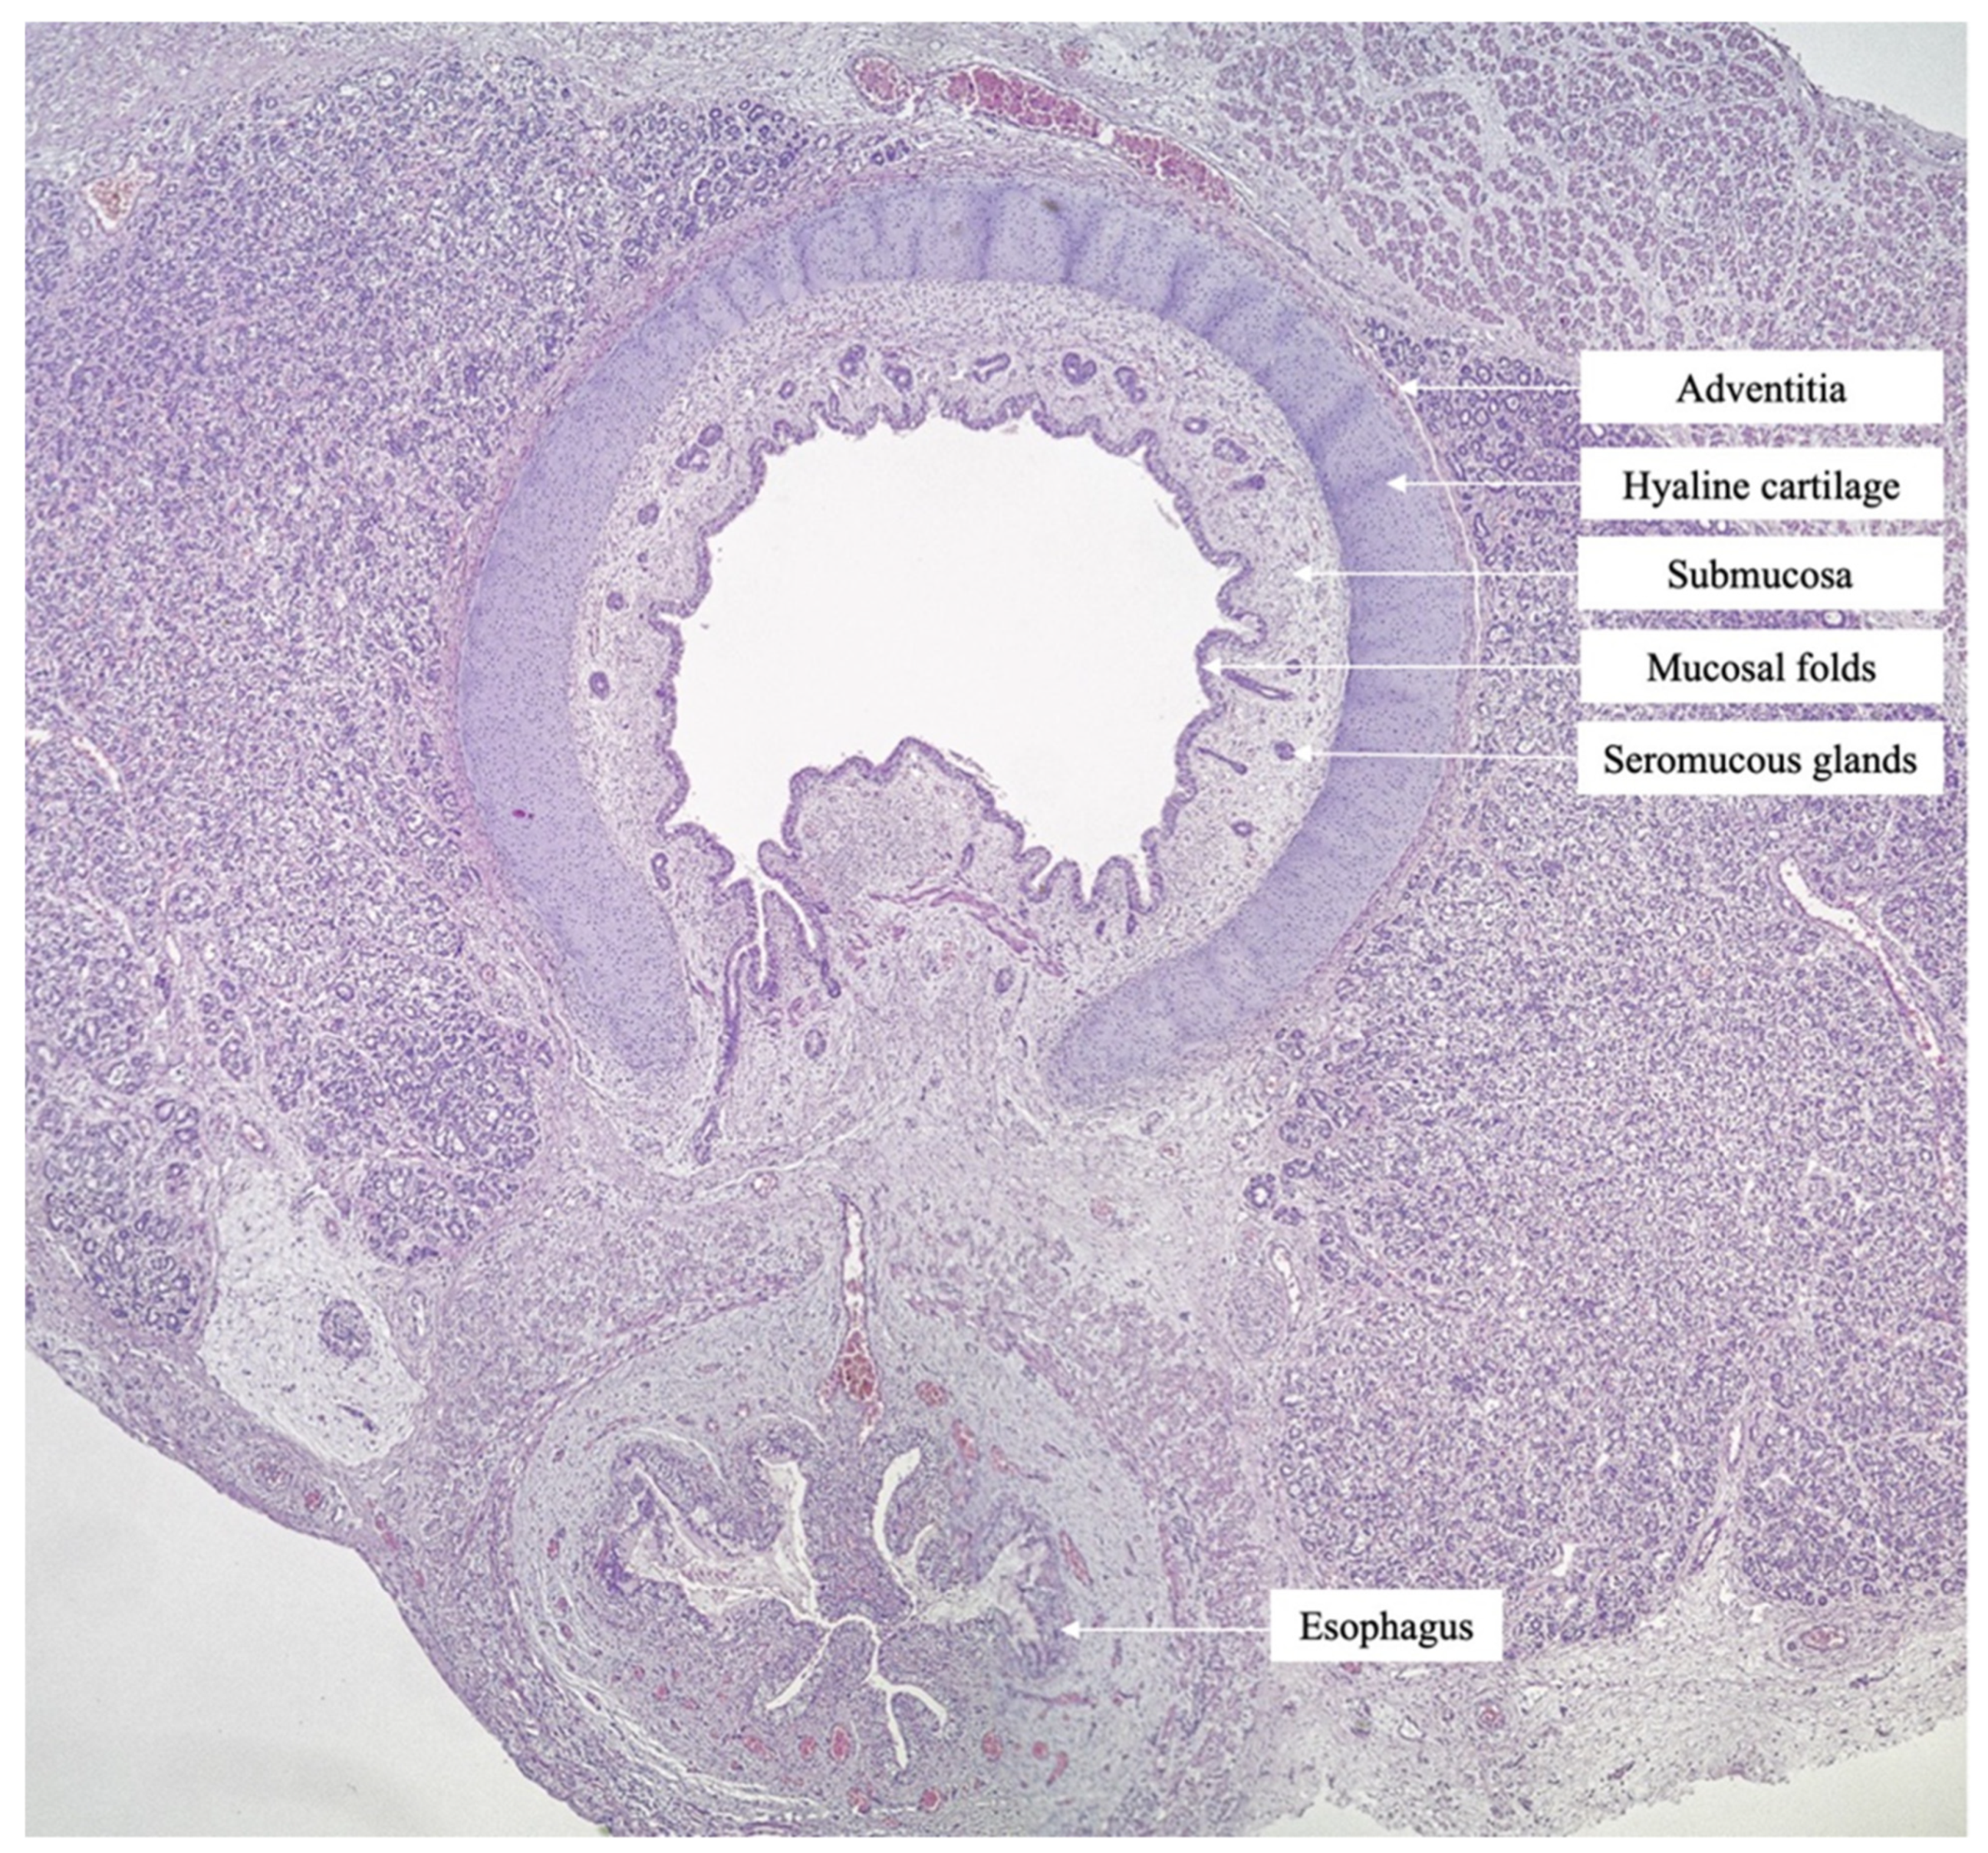

2. Case Report